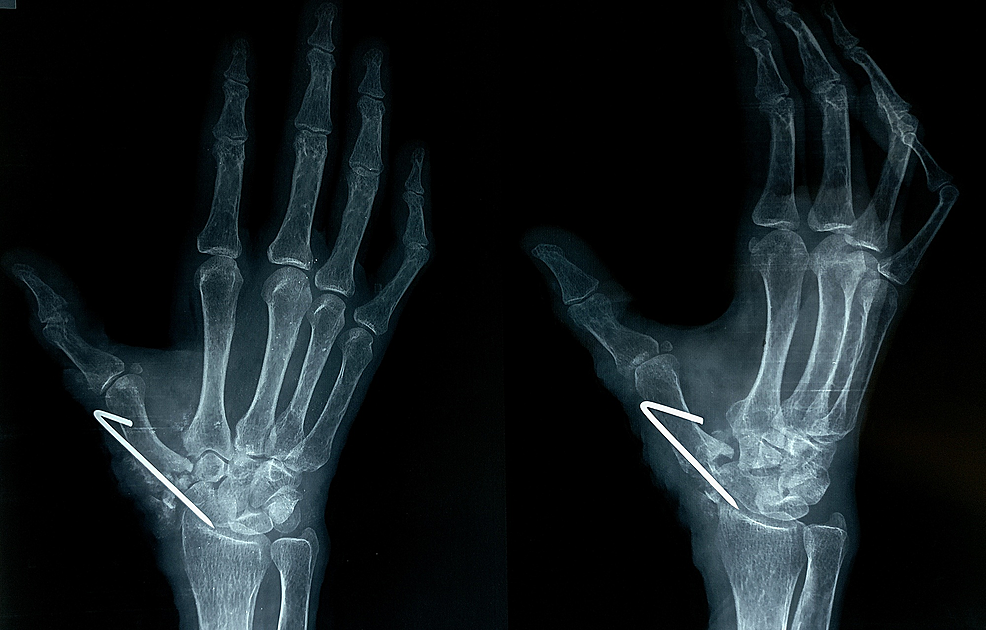

Figure 6 from Implant Arthroplasty for Proximal Interphalangeal Dip Joint Arthroplasty Symptomatic distal interphalangeal (dip) joint arthritis is frequently treated by arthrodesis, though. combined distal interphalangeal joint (dip) arthrodesis with proximal interphalangeal joint (pip) arthroplasty or arthrodesis. volar plate arthroplasty of the dip joint is one procedure that has been advocated for treatment of posttraumatic arthritis and chronic. 18 the technique uses small silicone implants that can be 19. Dip Joint Arthroplasty.